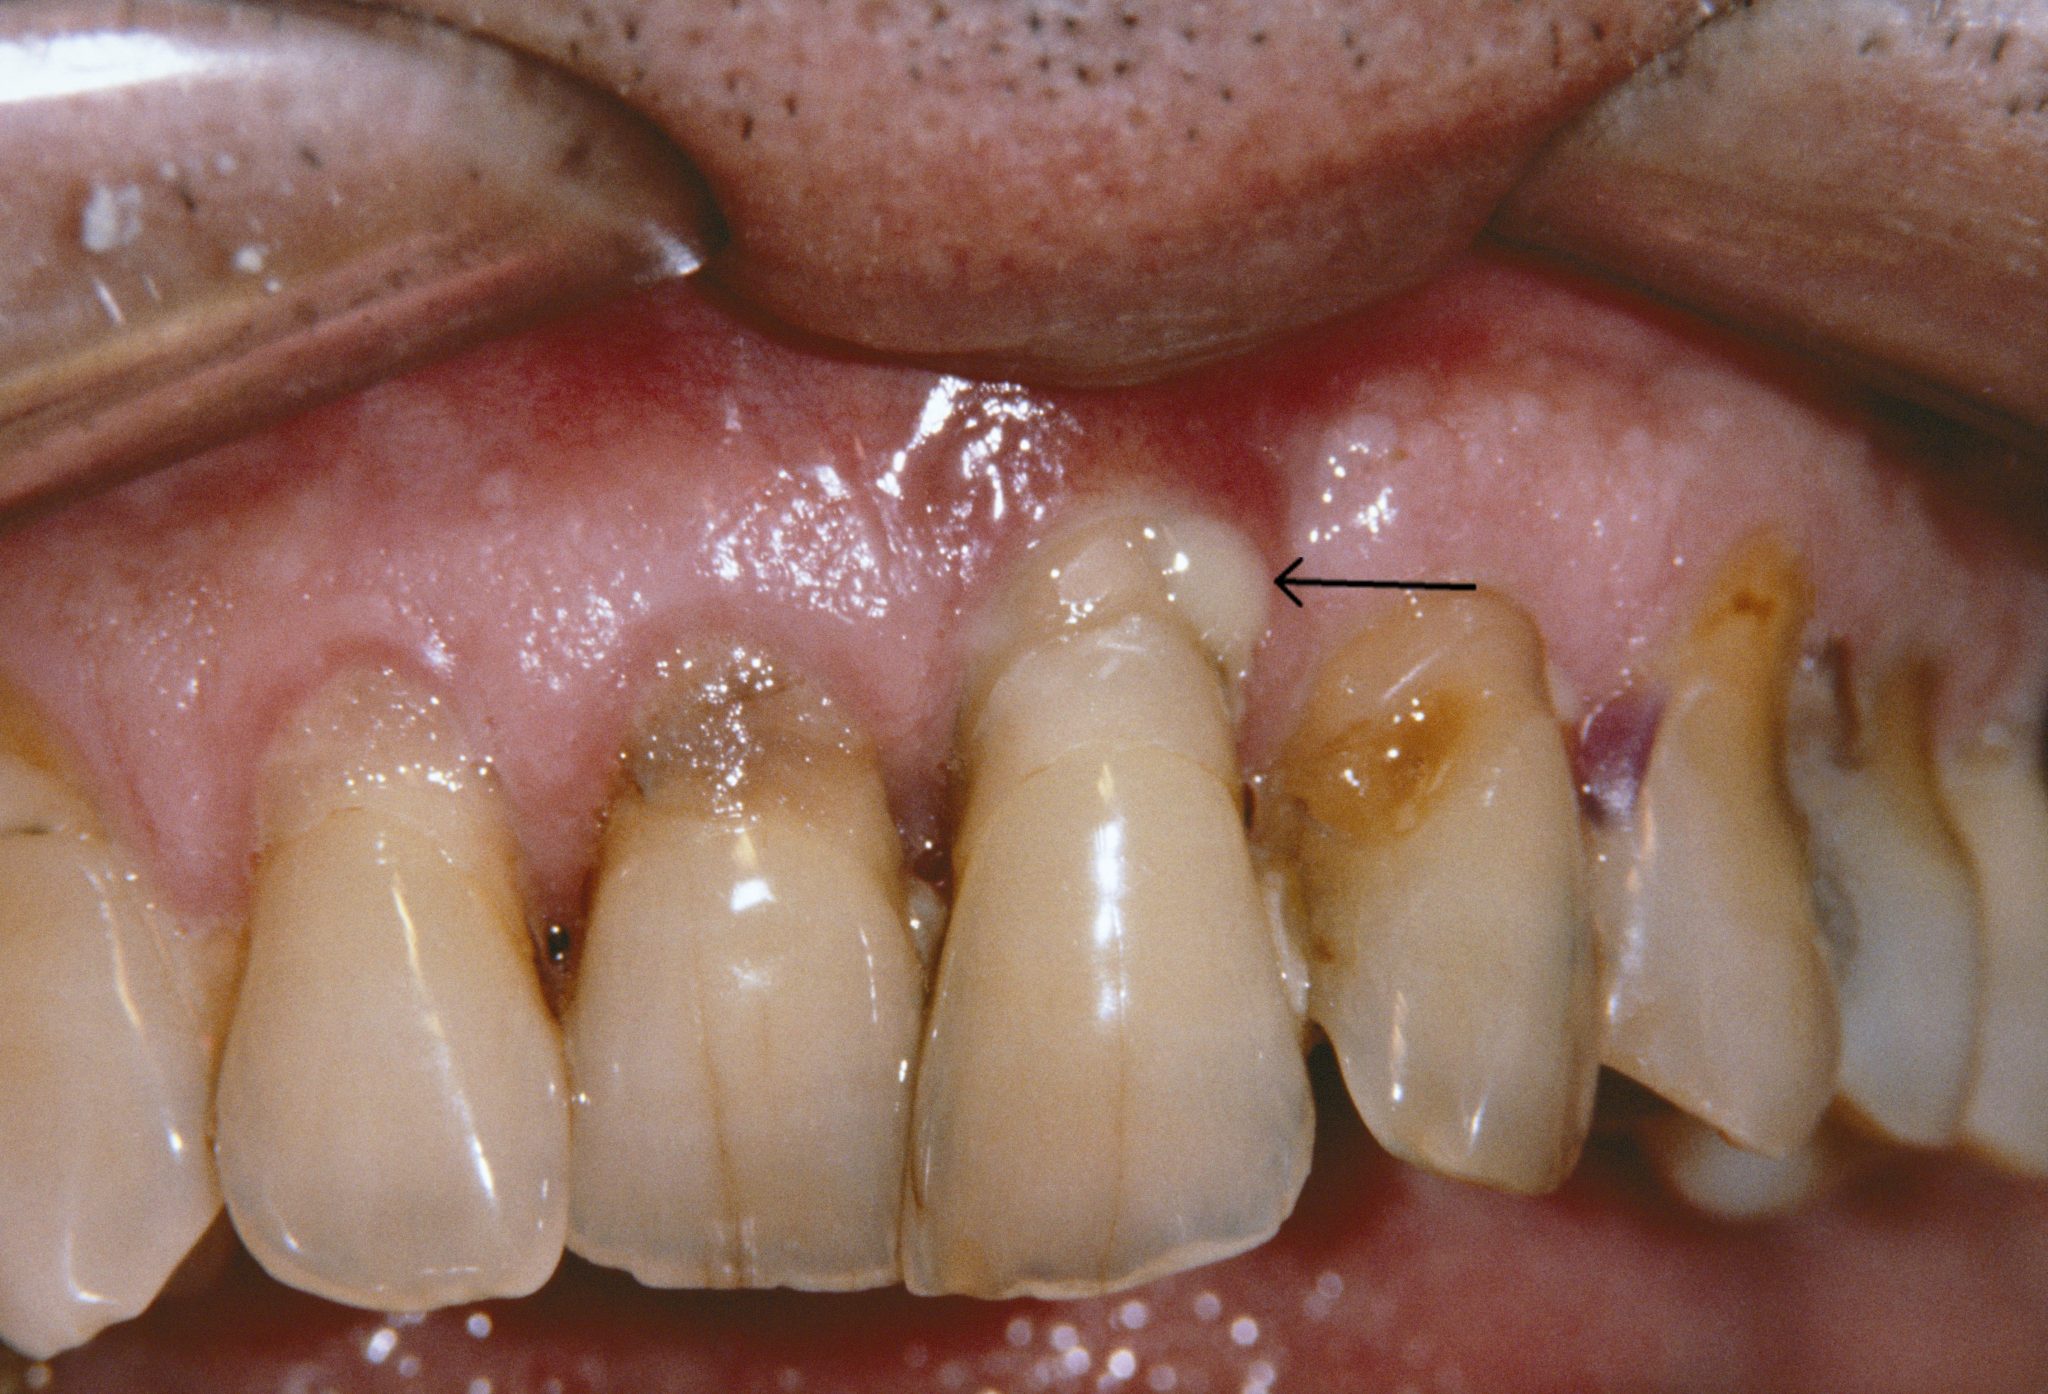

The alveolar bone and other tissues that support teeth are destroyed by periodontitis, a chronic inflammatory disease brought on by bacterial biofilm. Clinical attachment loss (CAL), pocket depths greater than 4 mm, bleeding on probing (BOP), and radiographic bone loss are used to make the diagnosis. Scaling and root planing are two methods used in treatment to reduce biofilm.

Periodontitis is an advanced stage of gum disease characterized by inflammation of the structures surrounding the teeth. It often originates from untreated gingivitis, where bacterial plaque buildup on teeth triggers inflammation of the gums. As periodontitis progresses, it can lead to the formation of pockets between the teeth and gums, which become breeding grounds for bacteria.

4. Receding Gums:

Gums that are pulling away from the teeth can create pockets where bacteria thrive, leading to further infection.

As periodontitis progresses, teeth may shift or become loose due to the destruction of supporting structures.